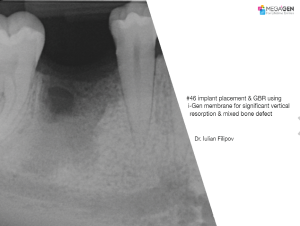

1 34 35 36